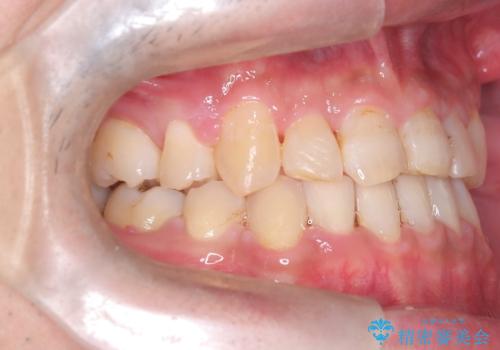

- 主訴:噛み合わせが反対になっているのを治したい

反対咬合と叢生改善のため、上下左右4番目の歯を抜歯し、審美装置にて矯正治療を行いました。